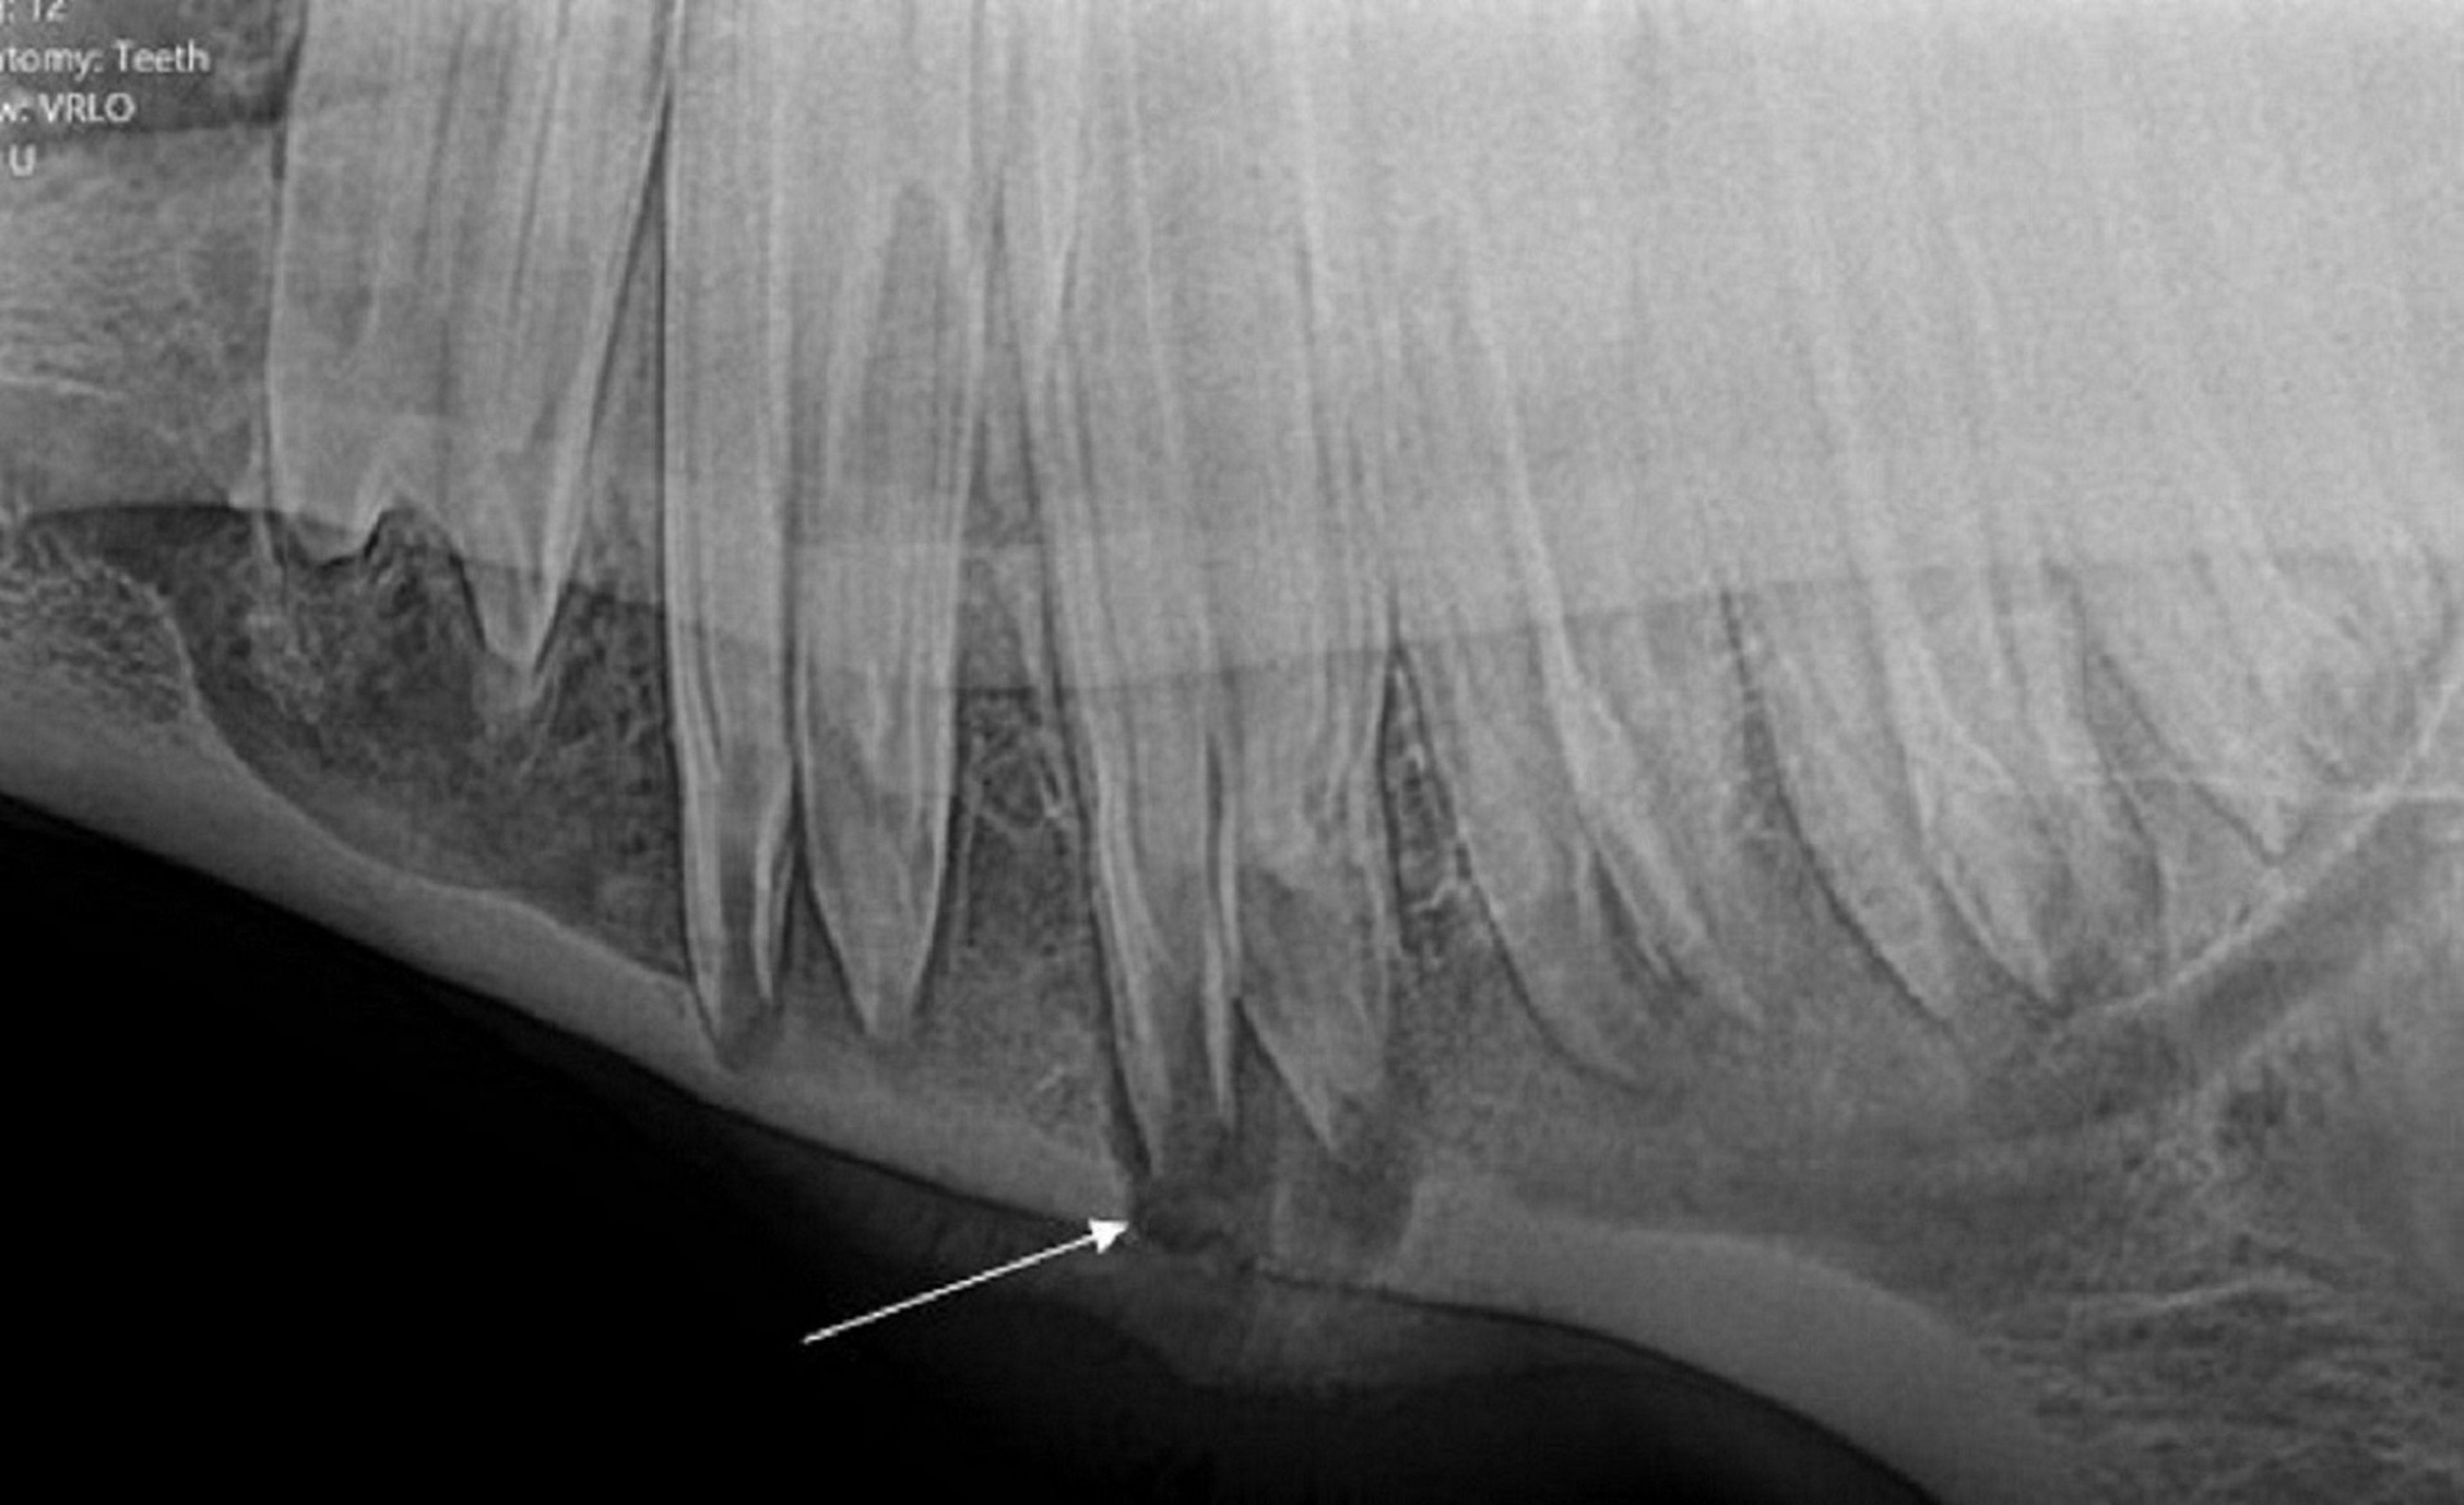

Periapical infection in horses most commonly affects the second and third cheek teeth (premolar 3 [Triadan 07s] and premolar 4 [Triadan 08s]) in both the upper and lower arcades. The pulp chamber of the teeth may become infected by various routes, including hematogenous (anachoretic pulpitis), periodontal, or from direct crown insult. In horses, hypoplasia of the cementum in the infundibula of the upper cheek teeth may predispose the animal to infundibular caries, leading to subsequent pulpitis and apical osteitis. The pathologic features of dental decay often affect tissues in the surrounding region; infection of the tooth may be accompanied by maxillary sinusitis, local cellulitis, periostitis, alveolar periodontitis, or fistula formation. Consequently, the specific tooth affected by apical infection in a horse or llama may be difficult to identify. Many animals are not examined until the infection is advanced. Tooth fractures discovered on examination may be secondary rather than primary. In some species (eg, the horse), apical osteitis and pulpitis may be initiated by abnormal eruption and dental impaction. The cause of apical osteitis in cattle and New World camelids may be similarly influenced.